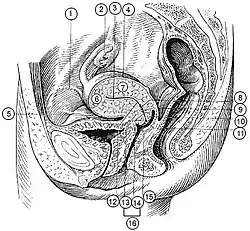

Additional images

14. Uterus: Parts: 15. Cervix; 16. Body and 17. Fundus. 18. Orifices: External and Internal; 19. Cervical canal; 20. Uterine cavity; Layers: 21. Endometrium; 22. Myometrium and 23. Perimetrium

24. Fallopian tube

30. Ovary

31. Visceral pelvic peritoneum: 32. Broad ligament (with 35. Mesometrium)

Ligaments: 36. Round

Blood vessels: 40. Uterine artery and veins

Other: 42. Ureter; 46. Internal iliac vessels (anterior branches); 48. Abdominal cavity

Schematic frontal view of female anatomy

Schematic frontal view of female anatomy

The arteries of the internal organs of generation of the female, seen from behind Median sagittal section of female pelvis

Median sagittal section of female pelvis (Description located on image page)